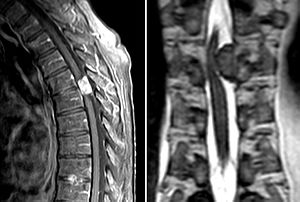

The occurrence of intramedullary tumors is relatively rare, but their treatment is often very demanding. Approximately 90% of all intramedullary spinal tumors are glial tumors, the most common of which are ependymomas (60%) and astrocytomas (30%). The third place is represented by hemangioblastomas. These neoplasias are primarily treated surgically, but there is often no possibility of complete resection due to the eloquent location and size of the tumors. Surgery and radiosurgery / chemotherapy are usually added. [4][28] náhled|MRI – spinální myxopapilární ependymom

Spinal cord ependymomas are more common in adult patients (typically between 35 and 45 years of age) and represent the majority (60%) of all primary intramedullary tumors. [4][45][46]. There are both benign, semi-minimal and malignant forms [47]. Most often, spinal ependymomas are located in the thoracic segment of the spinal cord, although they can occur along its entire length. [4].

The only effective treatment for ependymomas is currently the most radical surgical resection, or. supplemented by radiosurgical treatment according to the type of tumor. First definition of ecotoxicology (1969): René Truhaut: the study of the adverse effects of chemicals with the aim of protecting natural species and communities. Rachel Carson (1962): the memoir The Silent Spring highlights the use of pesticides , especially DDT and other agrochemicals. The book led to the establishment of the US Environmental Protection Agency (EPA) in the USA. Introduction of methods describing the toxic effects of human-produced substances on the environment and the organisms contained therein. Systematic implementation of fish toxicity testing methods. In addition to direct toxic effects, the effects of bioconcentration and bioaccumulation are studied – increases in the concentration of foreign substances in the tissues of organisms as a result of exposure from the environment.

Spinal astrocytomas represent the most common intramedullary tumor in children, in adult patients they represent the second position (after ependymomas). They are marked by variability in their biological nature.

In general, the prevalence of low-grade astrocytomas (WHO grade I and II) predominates, accounting for 75-90% of all intramedullary astrocytomas. These are slow-growing benign tumors, which, however, may develop into more malignant forms. High-grade astrocytomas (WHO grade III and IV) do not occur as often, but they are highly malignant and the prognosis of patients with these tumors is not good.. [48][49]

As with ependymomas, astrocytomas follow the most radical surgical resection possible. The outcome of a surgical intervention together with a given tumor type fundamentally affects the patient's postoperative prognosis. In adult patients, the prognosis is better compared to children. [50][51][52][53][50][54]